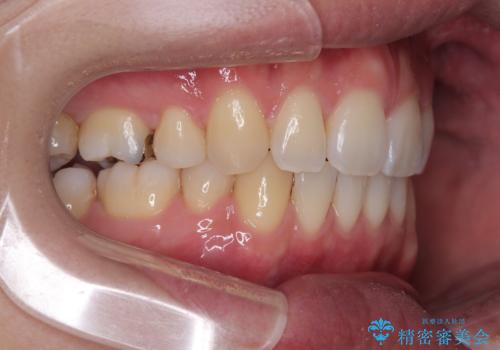

口元が出ているのが気になる。審美装置による抜歯矯正

- 口元の突出感と下の前歯のがたつきを主訴として来院された患者様です。

口元の突出感と叢生改善のため上下左右の第一小臼歯4本を抜歯し、ワイヤー装置にて矯正治療を行うこととしました。

なるべく目立たない装置が希望だったため、審美装置で治療を行いました。